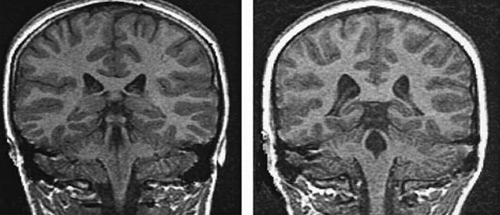

ΕΙΚΟΝΑ 1. Διευρυσμένες πλάγιες

κοιλίες σε ένα 11χρονο κακοποιημένο αγόρι με ΜΤΔΣ (Δεξιά), συγκριτικά με μάρτυρα

ίδιας ηλικίας και φύλου (Αριστερά).

Προσαρμογή από De Bellis, 1999

Στη μελέτη των De Bellis και συνεργατών βρέθηκε ότι κακοποιημένα παιδιά και

έφηβοι παρουσίαζαν μικρότερους ενδοκρανιακούς όγκους και περισσότερο διευρυμένες

πλάγιες κοιλίες (εικόνα 1) από ό,τι φυσιολογικοί μάρτυρες ίδιας ηλικίας και

φύλου.